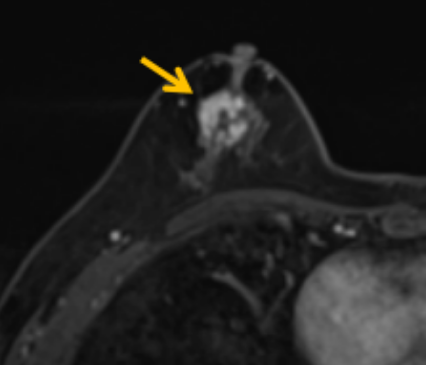

陳寶瑩評估圖像后發(fā)現(xiàn)病變?yōu)閮H僅在磁共振增強(qiáng)時顯示,為非腫塊樣病變,比較散,必須取得足夠多的組織才能確保病理檢查的準(zhǔn)確性,常用的核芯針活檢獲取的組織較少,因此最終確定了磁共振引導(dǎo)下行真空輔助抽吸旋切活檢。取得患者及家屬認(rèn)可后,陳寶瑩帶領(lǐng)團(tuán)隊(duì)開始進(jìn)行術(shù)前準(zhǔn)備。

針對患者乳房小固定難度大這一問題,陳寶瑩通過巧妙體位和固定器的調(diào)整,順利固定好乳房。經(jīng)過磁共振多模態(tài)掃描,陳寶瑩找出病變活性成分相對集中區(qū)域,精準(zhǔn)確定穿刺路徑,置入引導(dǎo)針、旋切針,到位后多角度旋切取出足量組織,拔除旋切針后即時行磁共振掃描,精準(zhǔn)取得組織且術(shù)區(qū)出血很少,遂加壓包扎,整個過程非常順利,旋切活檢后患者回家休息。兩天后隨訪,李女士沒有任何不適,五天后皮膚上幾毫米的小切口已經(jīng)愈合。最終病理結(jié)果證實(shí)為乳腺導(dǎo)管原位癌,為早期乳腺癌,為患者后續(xù)針對性治療奠定了基礎(chǔ)。